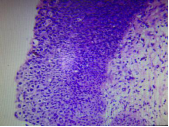

子宮頸上皮內瘤變

子宮頸上皮內瘤變(CIN)是指子宮頸上皮被不同程度異型性的細胞所取代。表現為細胞大小形態不一,核增大深染,核質比例增大,核分裂象增多,細胞極性紊亂。病變由基底層逐漸向表層發展。

根據其病變程度不同分為三級:Ⅰ級,異型細胞局限于上皮的下1/3,Ⅱ級,異型細胞累及上皮層下1/3至2/3,Ⅲ級,增生的異型細胞超過全層的2/3,包含原位癌。子宮原位癌是指異型增生的細胞累及子宮頸黏膜上皮全層,但病變局限于上皮層內,未突破基底膜。原位癌的細胞可由表面沿基底膜通過宮頸腺口蔓延至子宮頸腺體內,取代部分或全部腺上皮,但仍未突破腺體的基底膜,稱為原位癌累及腺體,仍然屬于原位癌的范疇。

CINⅠ級 CINⅡ級 CINⅢ級